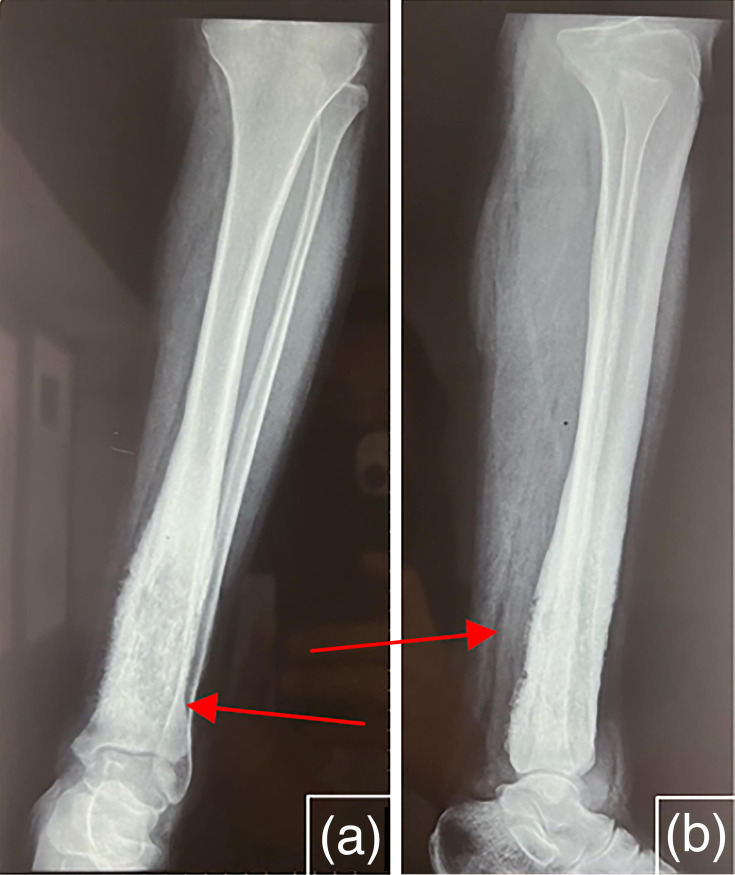

Tuberculosis is a major scourge, posing a serious public health problem in countries where it is endemic. Osteoarticular involvement accounts for 3-5% of all tuberculosis cases and 10-15% of extrapulmonary tuberculosis cases. We report a case of tibial osteitis caused by Mycobacterium tuberculosis in a 52-year-old female patient who presented to the trauma department at the Mohammed V Military Teaching Hospital with a painful swelling of the lower part of her left leg. Standard X-rays and computed tomography scans revealed bone involvement, specifically in the tibia. Additional investigations revealed pulmonary consolidation and splenic nodules. Microscopy (Ziehl-Neelsen staining), GeneXpert MTB/RIF and histopathological examination all returned positive results for M. tuberculosis. In an endemic context, any persistent and atypical bone lesion should raise suspicion of osteoarticular tuberculosis to enable rapid diagnosis and appropriate therapeutic management. In the absence of malignant tumours and other differential diagnoses, the diagnosis of skeletal tuberculosis must be considered, even in the absence of specific clinical signs.